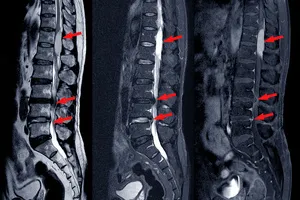

신경외과는 뇌, 척수, 말초신경 등 우리 몸의 신경계 전체를 다룹니다. 허리디스크의 경우 디스크가 신경을 눌러서 생기는 통증, 저림, 마비 등 신경학적 증상에 대한 전문적인 지식과 치료 경험이 풍부합니다. 특히 미세현미경이나 내시경을 이용한 디스크 제거술처럼 신경을 보존하면서 디스크를 제거하는 수술에 능숙하죠. 신경학적 이상 증상이 두드러지거나 MRI 검사에서 신경 압박이 심하게 확인될 때 신경외과 진료가 더 효과적일 수 있습니다.

- 주요 치료: MRI 검사, 신경차단술, 신경성형술, 고주파 수핵 성형술, 적극적인 운동 치료 및 재활

디스크가 완전히 파열되어 수핵이 튀어나오거나, 디스크 조각이 떨어져 나와 신경을 심하게 누르는 단계입니다. 극심한 통증과 함께 다리에 힘이 빠지거나(마비), 감각이 둔해지는 등 신경학적 이상 증상이 명확하게 나타납니다. 심한 경우 대소변 장애가 발생할 수도 있습니다.

- 주요 치료: 미세현미경 디스크 제거술, 내시경 디스크 제거술, 척추 유합술, 인공 디스크 치환술, 집중 재활 치료